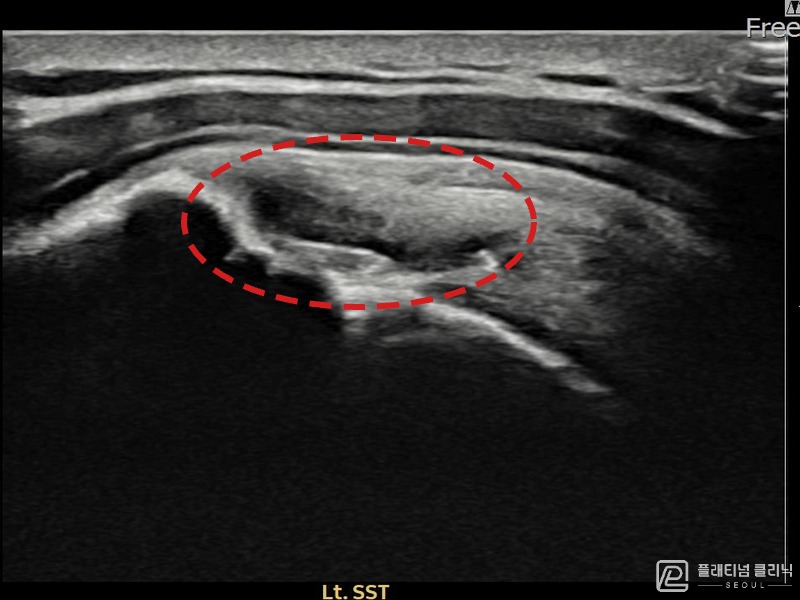

[촬영시기:22.10.06~22.11.14]

[어깨인대 축소봉합술] 좌측 어깨 극상근건 광범위 파열로 수개월간 일상생활이 어렵던 중 내원하셨습니다.